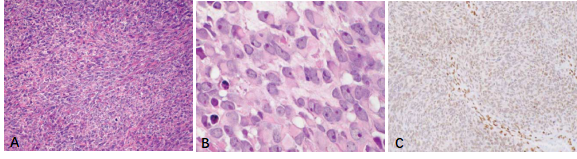

新近研發(fā)的針對SS融合蛋白連接處的特異性抗體SS18-SSX(克隆號E9X9V,圖1,引自參考文獻(xiàn)3)在滑膜肉瘤腫瘤細(xì)胞核呈中等至強(qiáng)陽性表達(dá)(圖2),其靈敏度和特異度分別達(dá)95%和100%[3, 4]。研究表明[5],SS18-SSX IHC在診斷SS方面和FISH等分子檢測方法具有很好的一致性(圖3,引自參考文獻(xiàn)5),甚至比其他方法檢測SS更有特異性,特別是在非典型FISH模式的病例中(圖4,引自參考文獻(xiàn)5),它與RNA測序結(jié)果有很好的相關(guān)性,有充分的證據(jù)說明此抗體在診斷SS方面已經(jīng)替代了FISH檢測方法。

圖2.雙相型滑膜肉瘤(A.HE染色,中倍放大)。免疫組化染色SS18-SSX(E9X9V)腫瘤細(xì)胞核彌漫強(qiáng)陽性(B.低倍放大,C.高倍放大)